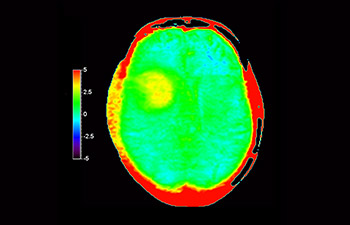

APTwイメージングでは、アミド基(NH)が対象となる。生体内のアミド基は、主にタンパク質やペプチドに含まれており、平均的には +3.5ppmの周波数に分布するとされる。アミド基のプロトンはバルク水から +3.5ppm離れた周波数帯に存在するため、交換プロトンの信号を抑制させる飽和パルスを +3.5ppmで選択的に照射する。飽和パルスによって信号が抑制されたアミド基のプロトンは、バルク水へ順次移動し、バルク水の信号を低下させる。飽和パルスの周波数を変化させながらバルク水の信号抑制を観察することで、間接的にアミド基を観察することができる(図1)。

CESTは、ごくわずかな共鳴周波数差(数100Hz)にあるプロトンを選択的に飽和させて画像化するため、静磁場B0(数十MHz)のわずかなズレでも、結果に大きな誤差が生じる。APTwイメージングでは、3D DIXON TSEシーケンスを用いB0補正を行っている。本シークエンスの利点は、3 point Dixonによる高精度のB0補正と撮像を一体化させB0不均一性に強い点と、スライスギャップなく3Dで広範囲の撮像が可能となった点である。これにより、B0不均一性に強く安定して広範囲のAPT強調像を撮像することができる⁴。